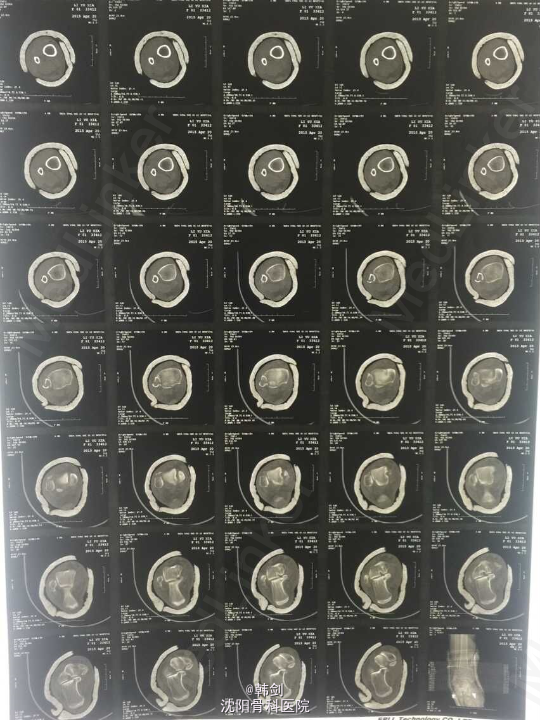

主诉:右踝外伤后肿痛、畸形、活动受限4小时. 病史:患者于2015年4月18日6:00,在家下楼时摔伤右踝,当即肿痛、畸形、活动受限,急来诊我院,经急诊拍片、阅片、查体后“右外踝骨折伴胫距关节脱位”为诊断收入院。病来无发烧,无头痛,头晕、头迷,无恶心、呕吐、无胸闷、气短等症,饮食 及二便正常.

查体:右踝皮肤完整无破溃,局部肿胀,畸形明显,可见皮下淤血,成青紫色,压痛阳性,可扪及骨擦音及骨擦感,异常活动存在,踝关节活动受限,末梢各趾活动自如,足背动脉搏动清。 辅查:WBC:6.91 10ˆ9/ L RBC:4.32 10ˆ12/L HGB:138g/L PLT:157 10ˆ9/ L ALT:24.0 U/L HBsAg:(-) 血型“O” RH(+) D-Dimmer:1.6 ug/ml 心电图:窦性心律,有束支传导阻滞,异常心电图。

初步诊断:右外踝骨折伴胫距关节脱位。 确定诊断:右外踝骨折伴胫距关节脱位。 补充诊断:右后踝骨折。 处理:1手法复位效果不佳 2患者入院后9天行手术治疗